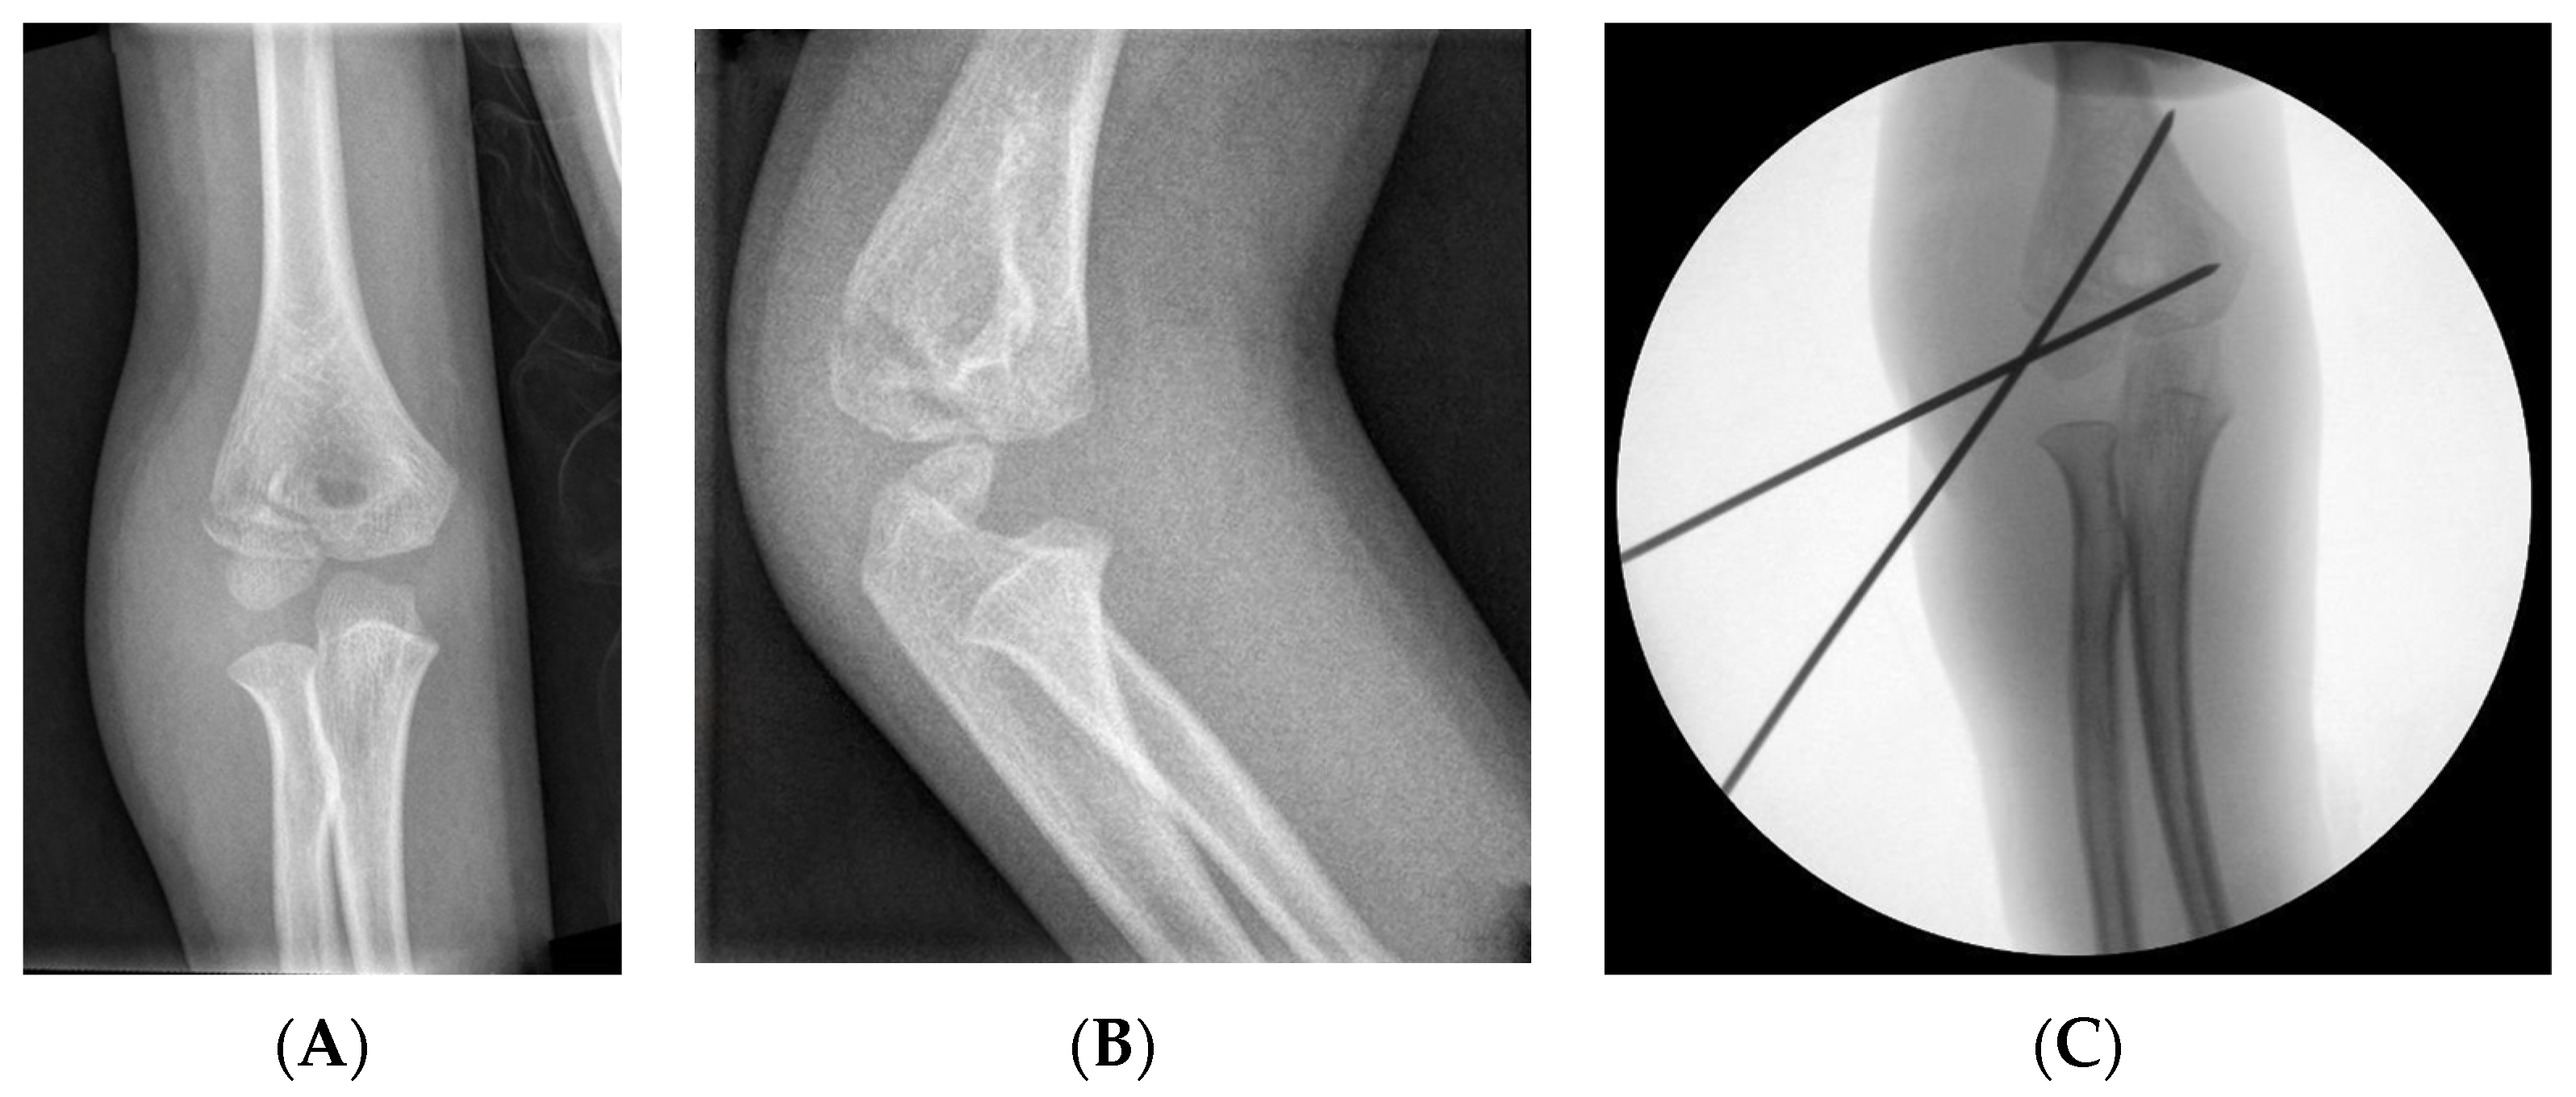

3.2.1. Closed Reduction

3.2.2. Open Reduction